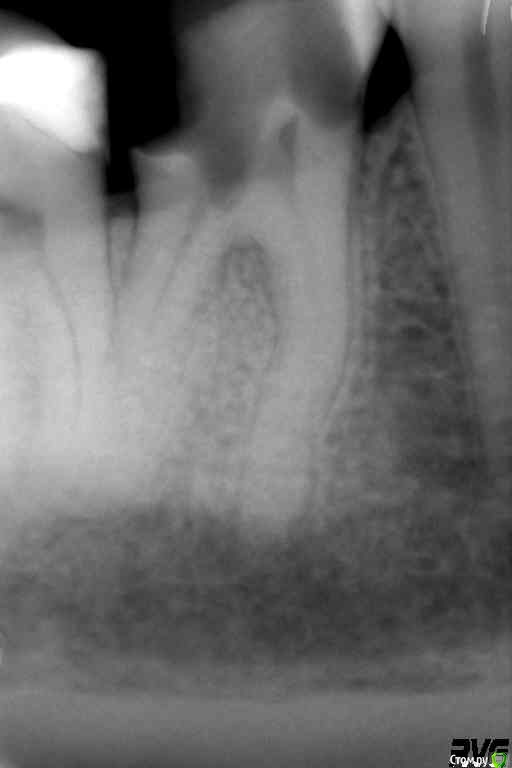

Джастина Опубликовано 2 ноября, 2020 Автор Поделиться Опубликовано 2 ноября, 2020 Вот рентген до заделки каналов: Вот после: Ссылка на комментарий